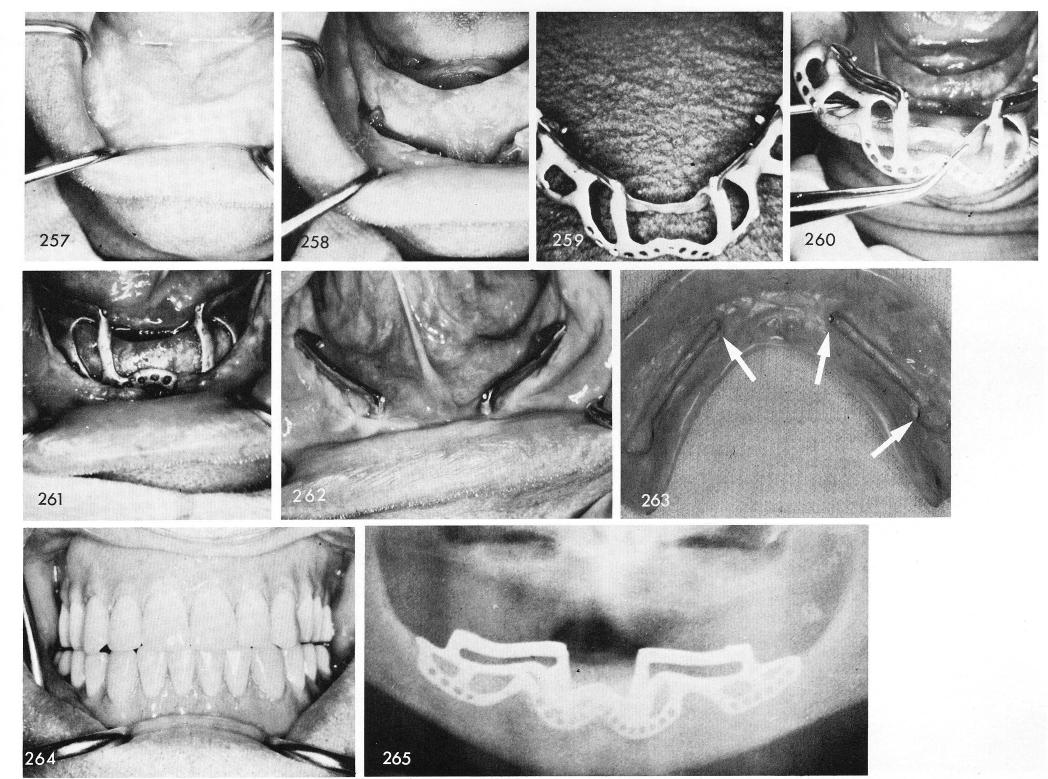

In this edentulous patient, fig. 257, some of the later designs were used. The bone was ex-posed, fig. 258, and the subperiosteal implant, with two horizontal bars instead of four posts was included in its design, figs. 259, 260, 261. Healing was excellent, and notice the tiny depressions in the anterior portion at the beginning of the horizontal bars and posteriorly and lingual to the bars, fig. 262. These act as a base for the spring-type ball bearings seen on the inside of this denture, called inter-coronal attachments, fig. 263, which gives excellent retention of the denture, fig. 264. Fig. 265 shows the new designed implant.

1 Mandibular prosthesis depression anterior,posterior,lingual to bar